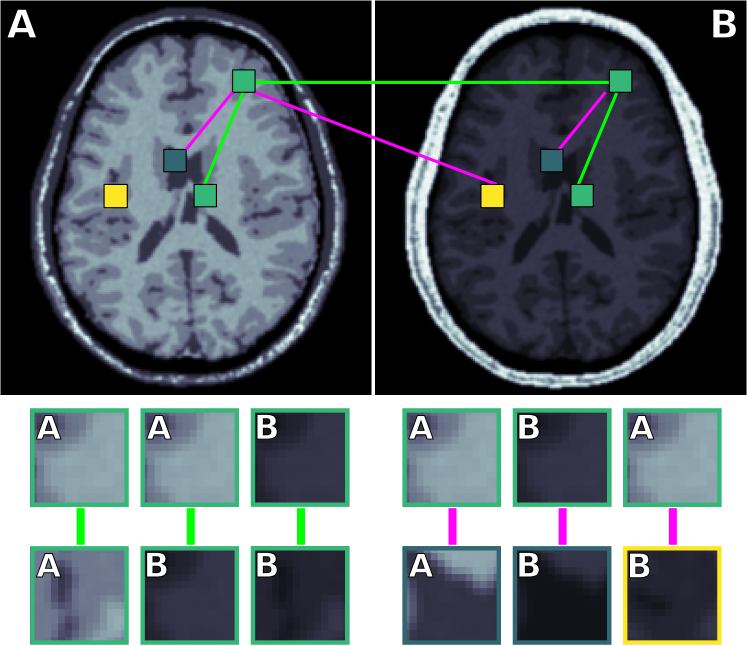

Figure 1 illustrates the process of selecting pairs of patches from different scanners. Consider a medical image from scanner A and scanner B, with 2 GM patches (green), 1 WM patch (yellow) and 1 CSF patch (blue) for each image. Using these patches we can generate the following pairs: a GM patch from A with another GM patch from A , a GM patch from A with a GM patch from B , a GM patch from B with another GM patch from B , a GM patch from A with a CSF patch from A , a GM patch from B with a WM patch from B , and a GM patch from B with a CSF patch from B . The bottom of the image shows examples of these 6 pairs of patches.

The pairs are concatenated into a dataset , where iterates over the pairs. In total, the number of combinations is , where refers to the number of source patches from the -th tissue and, likewise, refers to the number of target patches from the -th tissue. The number of pairs that can be generated is very large, even when only a small number of patches is available. For example, taking patches of 3 tissues from 4 source scans and 1 patch of 3 tissues from 1 target scan, results in pairs of patches that can be used for training the deep neural network.